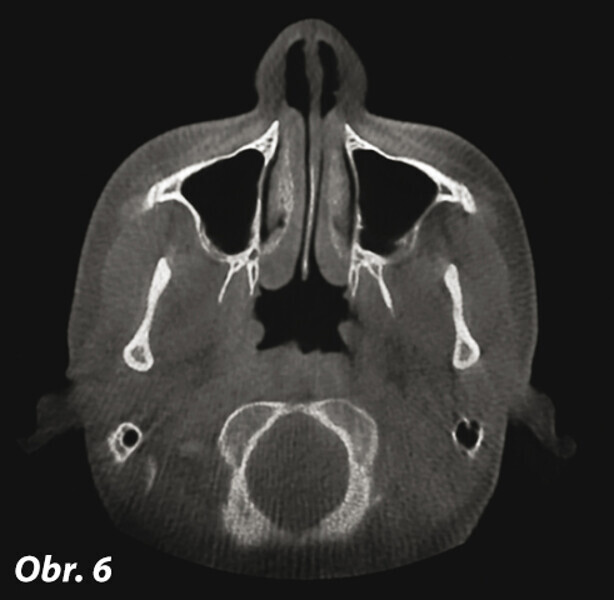

Význam 3D zobrazovacích systémů v současné ortodoncii